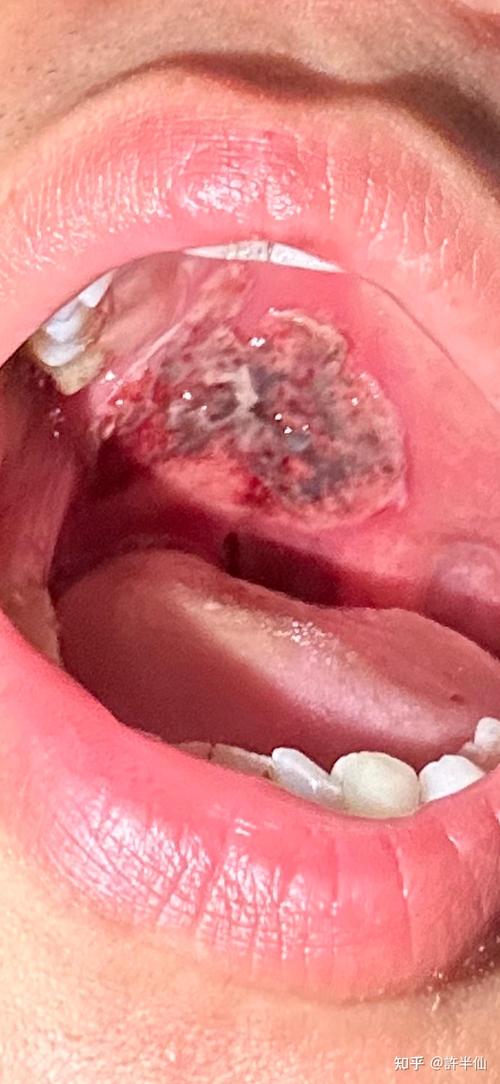

癌前病变或口腔癌

这是最需要警惕的情况!一些恶性肿瘤在早期就表现为一个不愈合的“溃疡”。

- 特点:

- 持续增大:溃疡会持续不断地长大,没有自愈倾向。

- 形态不规则:边缘不齐,呈菜花状或火山口状,基底有硬结感。

- 疼痛性质改变:早期可能不痛或微痛,但后期会发展为持续性、搏动性剧痛,并可能向耳部、头部放射。

- 其他伴随症状:

- 长期不愈:超过2-3周仍不愈合。

- 出血:轻微触碰就易出血。

- 麻木感:溃疡周围及下方区域可能出现麻木感。

- 功能障碍:影响张口、吞咽、说话。

- 淋巴结肿大:颌下、颈部淋巴结可能无痛性肿大、变硬。

- 常见部位:舌缘、口底、颊黏膜、软腭等部位是好发区。